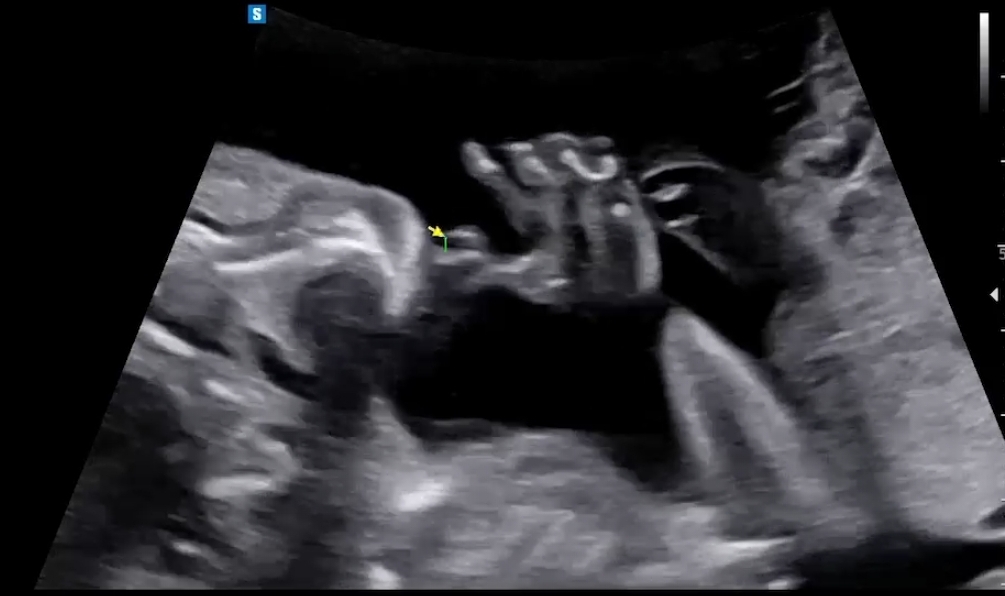

손가락 확인하려고 하는데, 아기들이 보통은 주먹을 쥐고 있다고 하더라구요. 근데 갑자기 인사하듯이 손바닥을 확 펼쳐 주었다가 다시 손을 빨더라구요ㅎㅎ